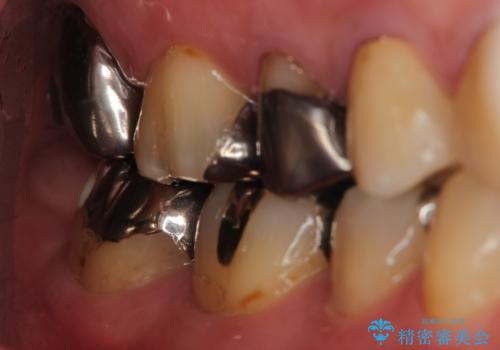

- 右下奥の銀歯3本をオールセラミッククラウンで治療した症例です。

右下6は失活(神経が死んでいる状態)していたため根管治療を行いました。